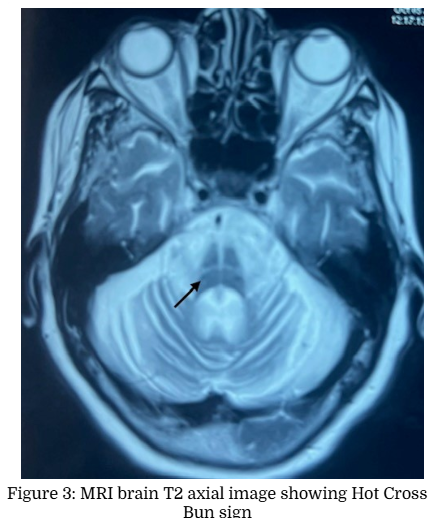

A 67-year-old lady presented with progressive swaying during walking and dysarthria of five years duration. She also noted bilateral upper limb incoordination for the last 2 years. She had occasional falls and urge incontinence. There was no history of any diplopia, dysphagia, weakness, rest tremor or sensory symptoms. There was no history of syncope but had constipation. There was no family history of similar illness. On examination her vitals were normal. Mini Mental Status Examination showed a score of 28 out of 30. Cranial nerve examination showed gaze evoked nystagmus and scanning dysarthria. She had hypomimia with mild bilateral appendicular rigidity. She had normal power in upper and lower limbs with normal deep tendon reflexes. Plantars were flexor. She had bilateral finger nose incoordination and gait ataxia with mild postural instability. Autonomic system examination showed a postural drop of blood pressure of 40/20 mm of Hg. She was treated with carbidopa-levodopa combination without much improvement. In view of symmetrical parkinsonism with poor L-dopa response, bilateral cerebellar signs and postural hypotension, a diagnosis of Multiple system atrophy- cerebellar type (MSA-C) was made and MRI brain was taken. Brain MRI axial T2 weighted images showed Hot Cross Bun Sign (HCBS) and vertical T2 hyperintensity in Pons. There was corresponding hypointensity in T1 weighted images Figure (1 to 4).

The hot cross bun sign (HCBS) is a radiologic finding describing a cruciform T2 hyperintense signal on axial MRI of the pons, classically described in MSA. The underlying pathophysiological process is considered to be atrophy of pontine neurons and transverse pontocerebellar fibers with sparing pontine tegmentum and corticospinal tracts [2]. It is also reported in patients with spinocerebellar ataxia (SCA 1, 2, 3, 6, 7, 8, 10, 17, 23, 31, 34, 42), progressive multifocal leukoencephalopathy, paraneoplastic cerebellar degeneration from a burned-out testicular tumor, leptomeningeal metastases from breast cancer, bilateral middle cerebellar peduncle infarction, cerebrotendinous xanthomatosis, fragile X tremor ataxia syndrome (FXTAS) and variant Creutzfeldt-Jakob disease [3]. HCBS is graded as Grade 0 (No signal changes), Grade 1 (vertical T2 hyperintensity in ventral pons) and Grade 2 (cruciform hyperintensity in pons) in axial T2 weighted MRI brain images [4]. It is reported that the HCBS had a high specificity of 98% to 99% and a high positive predictive value of 94% to 99% for MSA‐C, but the sensitivity was only 45% to 68%. Some of the immune mediated cerebellar ataxia like anti‐Homer 3, anti-Ri and anti Kelch like protein 11 can mimic the MSA‐C phenotype and do not necessarily have a rapid progression [5]. HCBS also has been described in medulla in adult-onset Alexander’s disease [6].